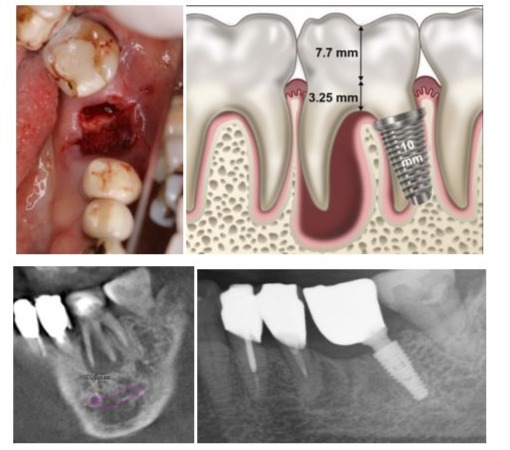

Treatment of a Type D Socket in the Mandible: Case 8

A type D socket does not allow implant stability with a WDI, which cannot be engaged in the outer wide periphery wall, has little to no septal bone, but one of the root sockets and buccal bone remains (Figure 2a,b). If even just one of the root sockets remains it should be considered a good candidate for implant placement (Figure 2a-d).

Figure s. 2a to 2d: a. A healthy 74-year-old female patient occupied housewife who visited for gingival swelling. A type D socket after the tooth extraction; b. A schema of an implant placement in the type D socket. A slight tilt might allow for the use of an implant longer than 10mm. The schema was created based on fig.3 of reference 4; c. A preoperative treatment plan with sagittal tomographic images. Fortunately, the distal root is small and short; d. A panoramic radiograph cut out 3 years after the surgery.

In many cases, full-thickness mucosal elevation is prepared to check for remaining alveolar bone, dissection of the socket and the narrow apical part of the root socket, and, in some cases, the socket may break during drilling, requiring a switch to type E socket treatment. However, there could be some problems with type D sockets, such as cantilever morphology leading to poor hygiene, food traps, irregularly screw access opening, and biomechanics that can arise when installing an implant into a residual root socket. The original report also explained that there will an erratically shaped crown with a cantilevered portion and/or a positioned screw access opening to redirect the opening [4]. The authors do the following to mitigate these shortcomings. For the cantilever morphology, before initial socket drilling, the bar should enter along the socket, correcting the direction of osteotomy toward the central occlusal table as much as possible, continuing until final drilling and installing the implant in the direction. These procedures improve screw access positioning, reducing the cantilever and allowing one to make closer to a regular crown shape. Regarding hygiene and food traps, during surgery, the buccal measurement and the height of the bone edge and the lingual side are recorded at the cantilever equivalent part, and based on them, the bone healing form is predicted. A form with a 3-mm mucosal thickness is added to this form, and a saddle-type shape that is slightly convex on the mucosal surface for easy access by dental floss is also added to the mucosal surface of the extension part according to this form (Figure. 2d) (in the case of final restoration placed within 3 weeks).